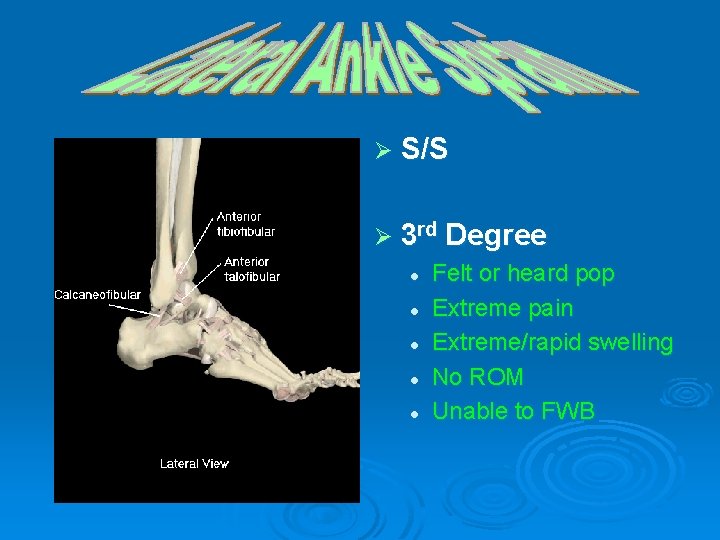

Ø 3 rd Degree Ankle Sprain Rupture of ligaments (ATF, CF, PTF) Ø Consider a FX Ø X-ray is mandatory Ø

Ø S/S Ø 3 rd Degree l Felt or heard pop l Extreme pain l Extreme/rapid swelling l No ROM l Unable to FWB